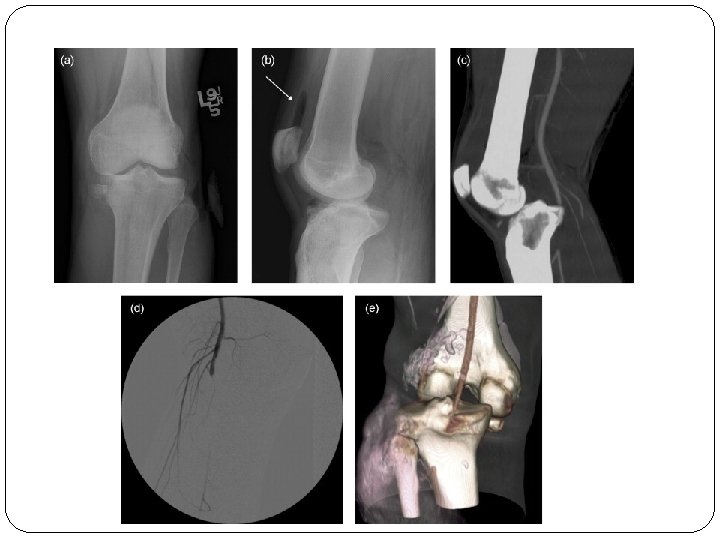

Dislocation- Knee Injury to popliteal artery and vein is common Peroneal nerve injury in 20 -40% of knee dislocations Associated with ligamentous injury Anterior (31%) Posterior (25%) Lateral (13%) Medial (3%)

Clinical Features & Mx Paraesthesia/numbness Injured limb cold, cyanosed, pulse weak/absent Call for help! Remove all bandages and splints Reduce the fracture/ dislocation and reassess circulation If no improvement then vessels must be explored by operation If vascular injury suspected angiogram should be performed immediately